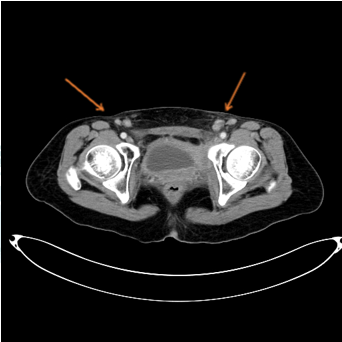

左侧髂内外血管旁、双侧腹股沟区

还有肿大淋巴结

但由于患者双侧腹股沟淋巴结及左侧髂血管旁淋巴结肿大,为此,我院为其安排了B超引导下双侧腹股沟淋巴结以及膀胱肿瘤活检术,进一步协助诊断。所幸结果显示均未见恶性肿瘤性病变。而根据我院影像资料、多次活检病理结果,暂不考虑患者是肿瘤复发。这个结果可把患者高兴坏了,也对医院很感激。